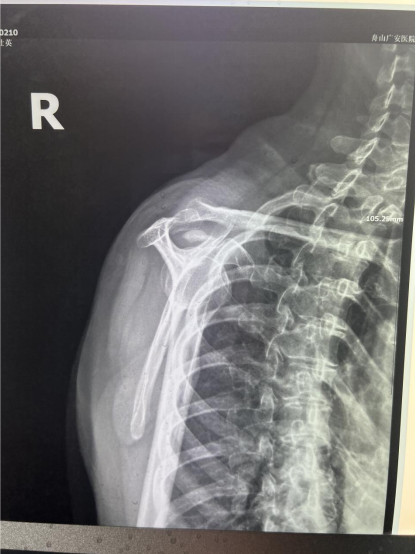

贺大妈慕名来广安医院找罗军主任就诊,面对罗医生,贺大妈哭诉:“罗医生,我真想剁下自己的这只胳膊。”罗军主任根据患者的症状拍片,诊断为冈上肌钙化性肌腱炎,随后,罗医生为李大妈进行了肩关节镜微创手术,竟从她的右肩“挤”出“牙膏”。

临床数据显示,10个肩痛女性患者中可能就有1人“中招”,且极易和肩周炎混淆,这就是“钙化性肌腱炎”。

钙化性肌腱炎是一种和肩周炎非常相像的疾病,但发病原因却大不相同。这种病是因为钙盐沉积诱发炎症反应。钙盐沉积可以发生在全身各个部位,大多原因不明,可能与代谢障碍、关节软骨损伤、随年龄老化而退变的关节等因素相关。

钙化性肌腱炎是一种自限性疾病,就是疾病发生发展到一定程度后,经长期机体调节能够控制病情发展并逐渐恢复痊愈。它分为四个阶段:钙化前期、钙化形成期、钙化吸收期、钙化后期,往往在“钙盐斑块”吸收时,疼痛最剧烈,贺大妈就正处于“吸收期”。